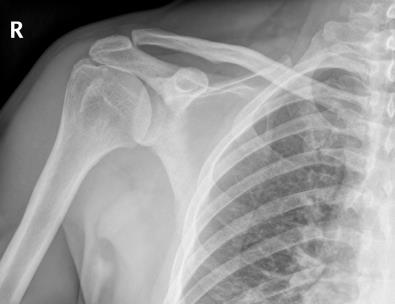

Chẩn đoán

Hỏi bệnh sử và khám thực thể.

Chụp cắt lớp vi tính (CT Scan), chụp cộng hưởng từ (MRI), chụp x-quang